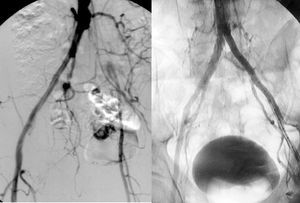

Cirugía de revascularización. La afectación difusa, extensa se trata de forma óptima habitualmente mediante el implante de una prótesis aórtica unifemoral o bifemoral (figs. 5 y 6). Se trata de una técnica de efectos conocidos, bien sistematizada y que ofrece unos resultados en términos de permeabilidad superiores al 85 y el 80% al cabo de 5 y 10 años, con cifras de mortalidad operatoria inferiores al 5%4. Sin embargo, es una cirugía arterial mayor y precisa cuantificar el riesgo quirúrgico para seleccionar a los candidatos más adecuados. En aquellos pacientes de alto riesgo o con un abdomen hostil (múltiples reintervenciones, radioterapia previa, infección activa, etc.) la intervención se realiza mediante las técnicas denominadas «extraanatómicas», que permiten la revascularización de las extremidades por trayectos no anatómicos, y con una menor agresión. Los más utilizados son la cirugía de derivación axilounifemoral o bifemoral, y la femoro-femoral. Ambos tipos de cirugías de derivación se tunelizan por vía subcutánea, la primera por la región lateral del tórax y el abdomen, y la segunda por la región suprapúbica. Pueden realizarse con anestesia locorregional. Las cifras de permeabilidad de las cirugías de derivación extraanatómicas son inferiores, con oscilaciones entre el 40 y el 70% a los 5 años, según la indicación clínica4. Por esta razón, raras veces se indican en ausencia de isquemia crítica.

Fig. 5. Arteriografía que muestra una oclusión aortoiliaca extensa y el resultado tras la realización de una cirugía de derivación aortobifemoral.